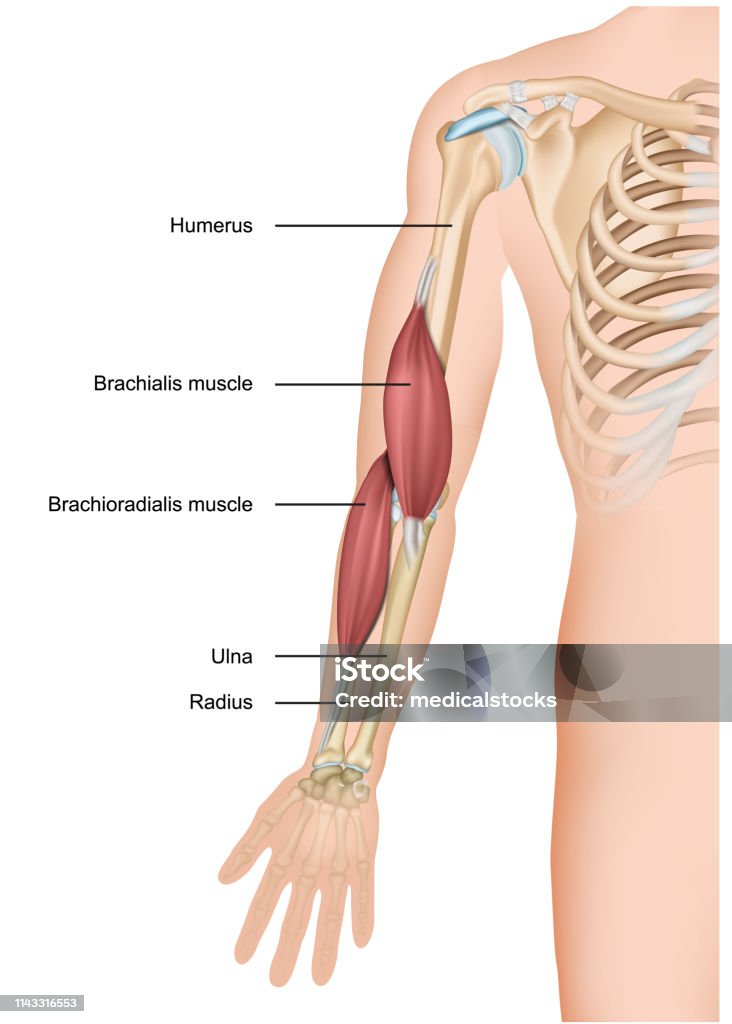

Анатомия и функции мышцы brachioradialis